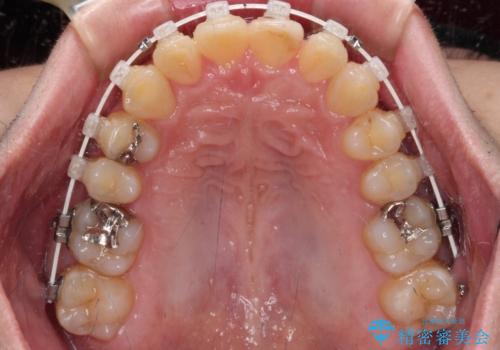

- 矯正装置

- 審美装置

- 1年4ヶ月

- 10-30回

歯ぎしりができないくらい強い食いしばりの咬合状態であったため、奥歯の歯軸を起き上がらせることで咬合を挙上させ、歯ぎしりができるようにしていくこととしました。

インビザラインでの矯正治療も可能でしたが、自己管理の煩わしさを嫌ってワイヤー装置による矯正治療を行うこととしました。